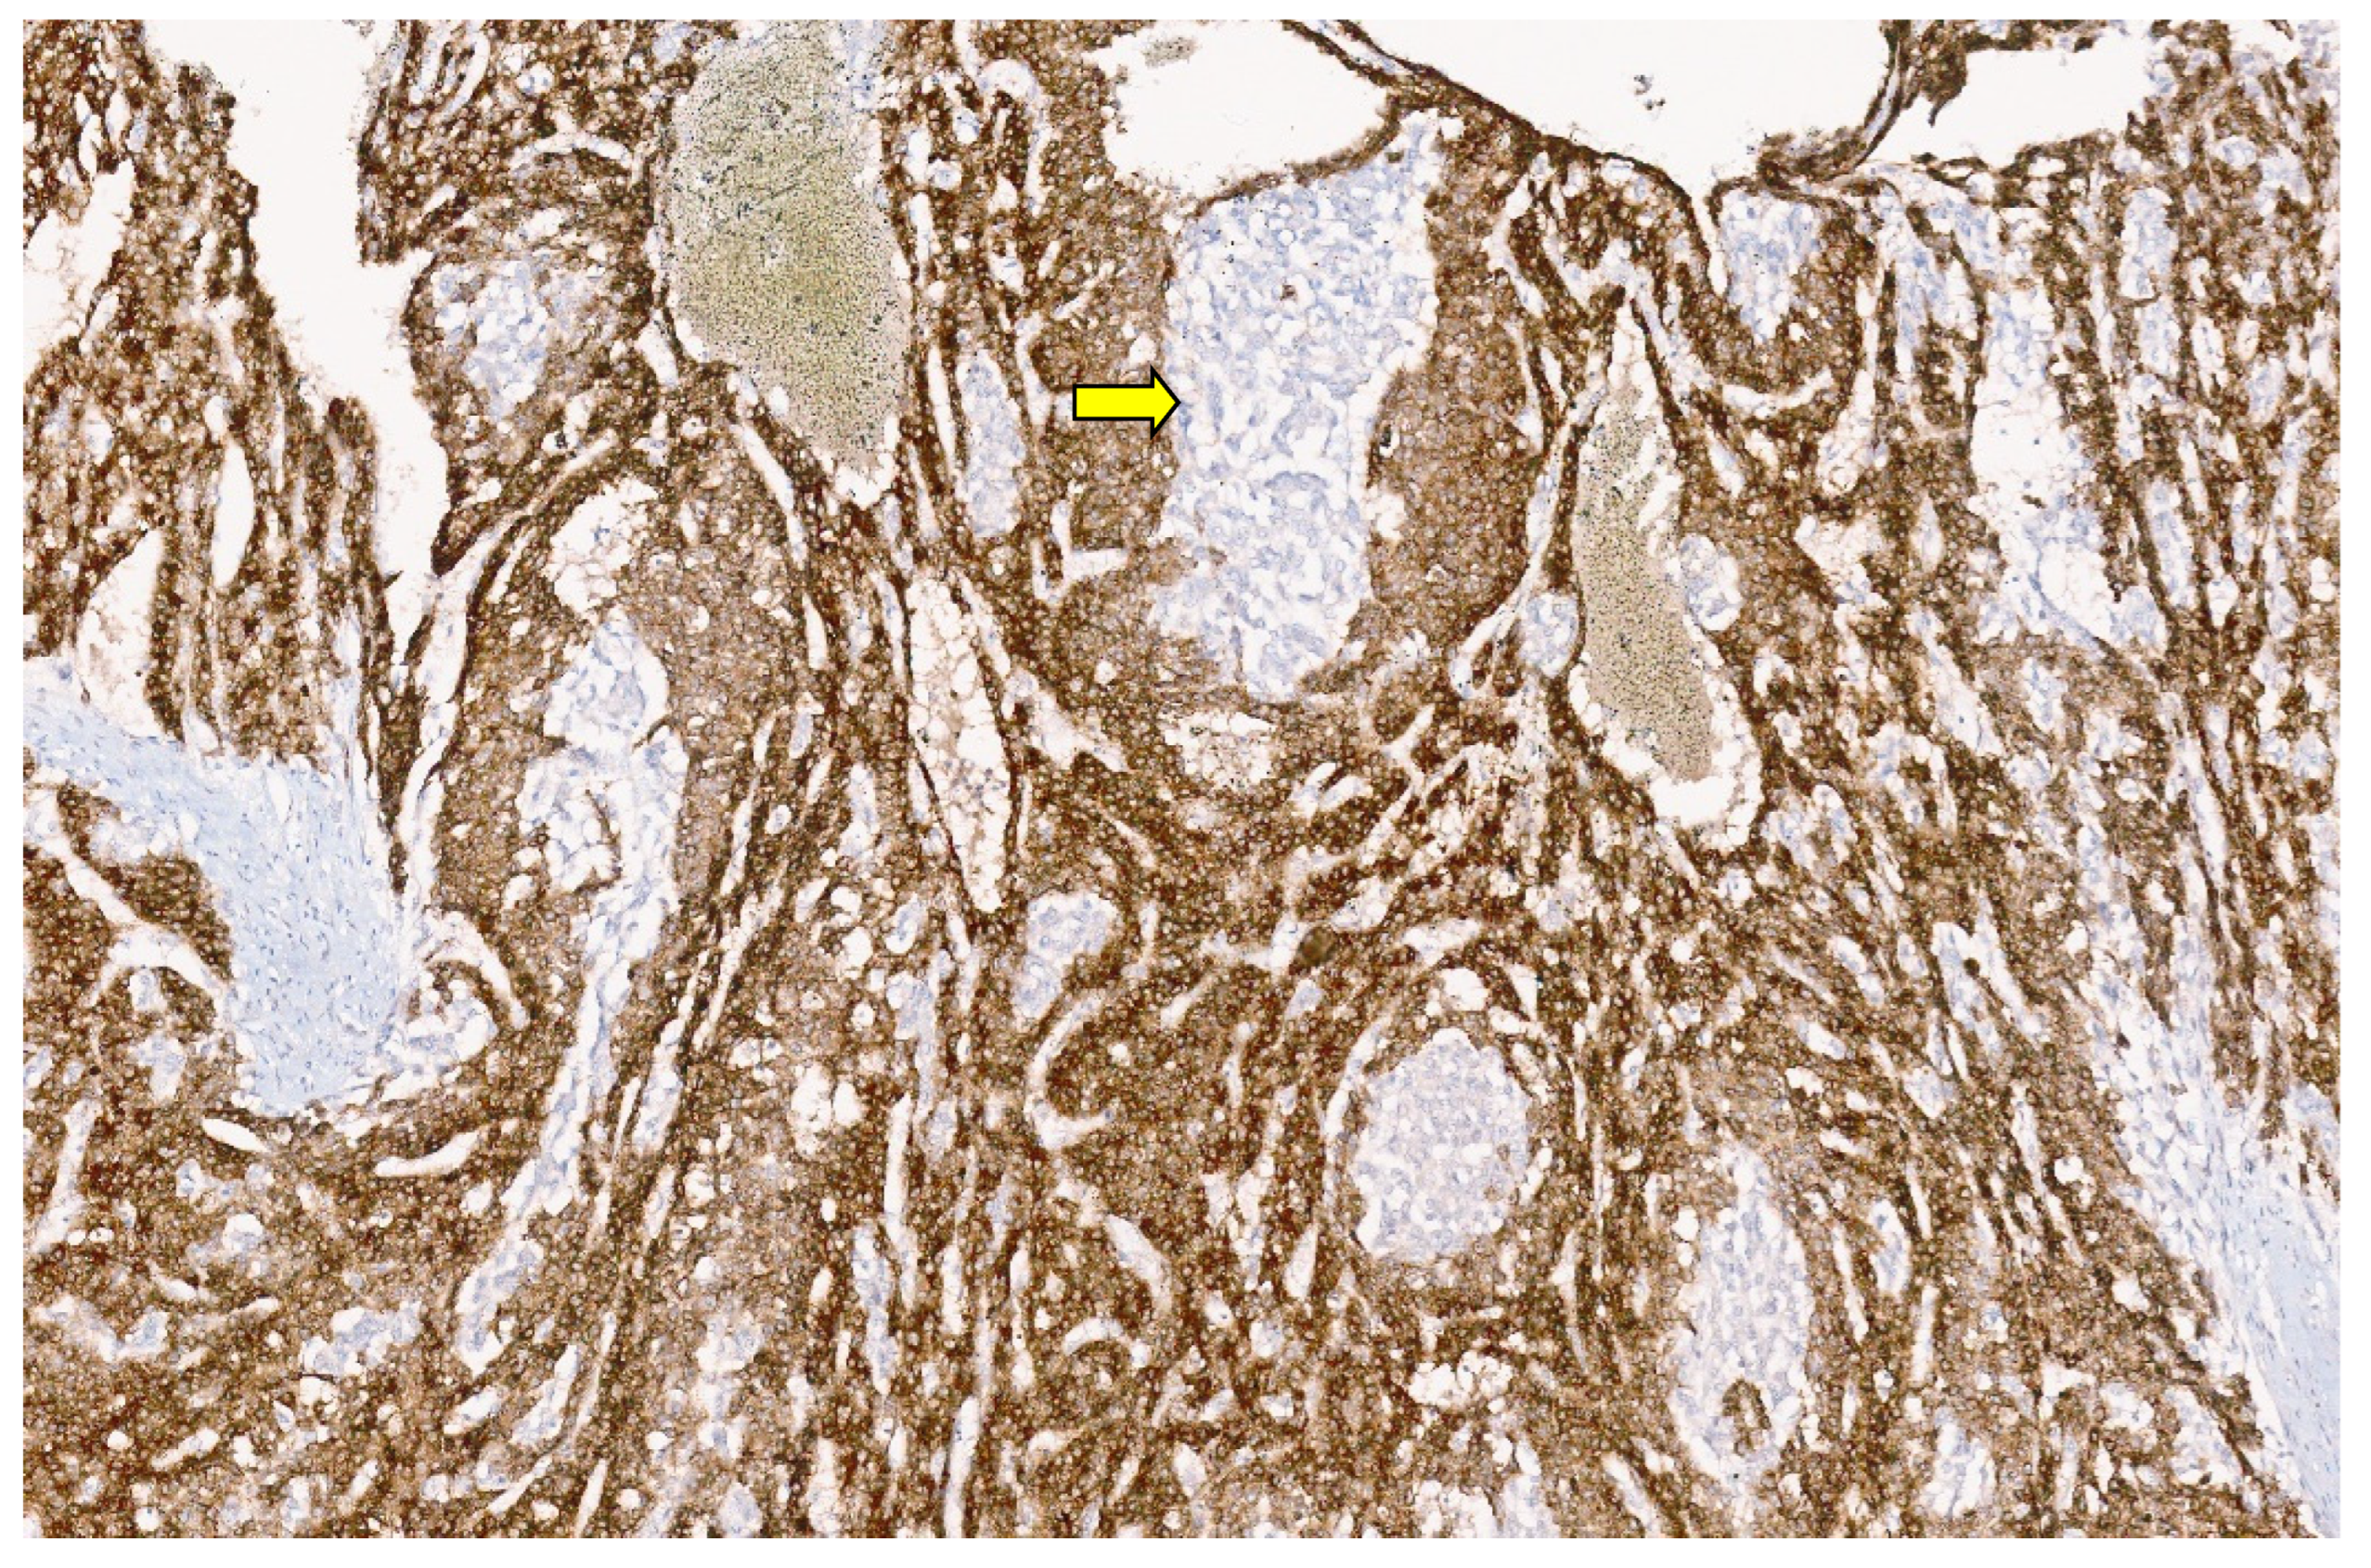

4.3. Pathology

12.3. Pathology